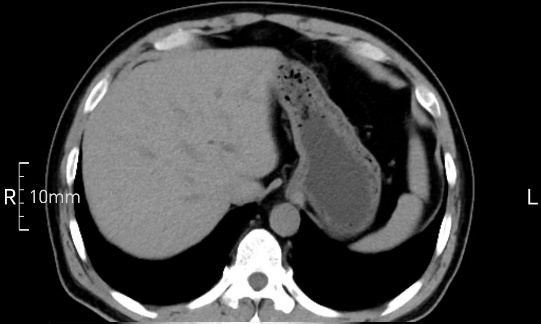

看看下面三幅便知遵醫(yī)囑的重要性。

沒(méi)禁食,胃內(nèi)全是食物,導(dǎo)致胃壁顯示不清。